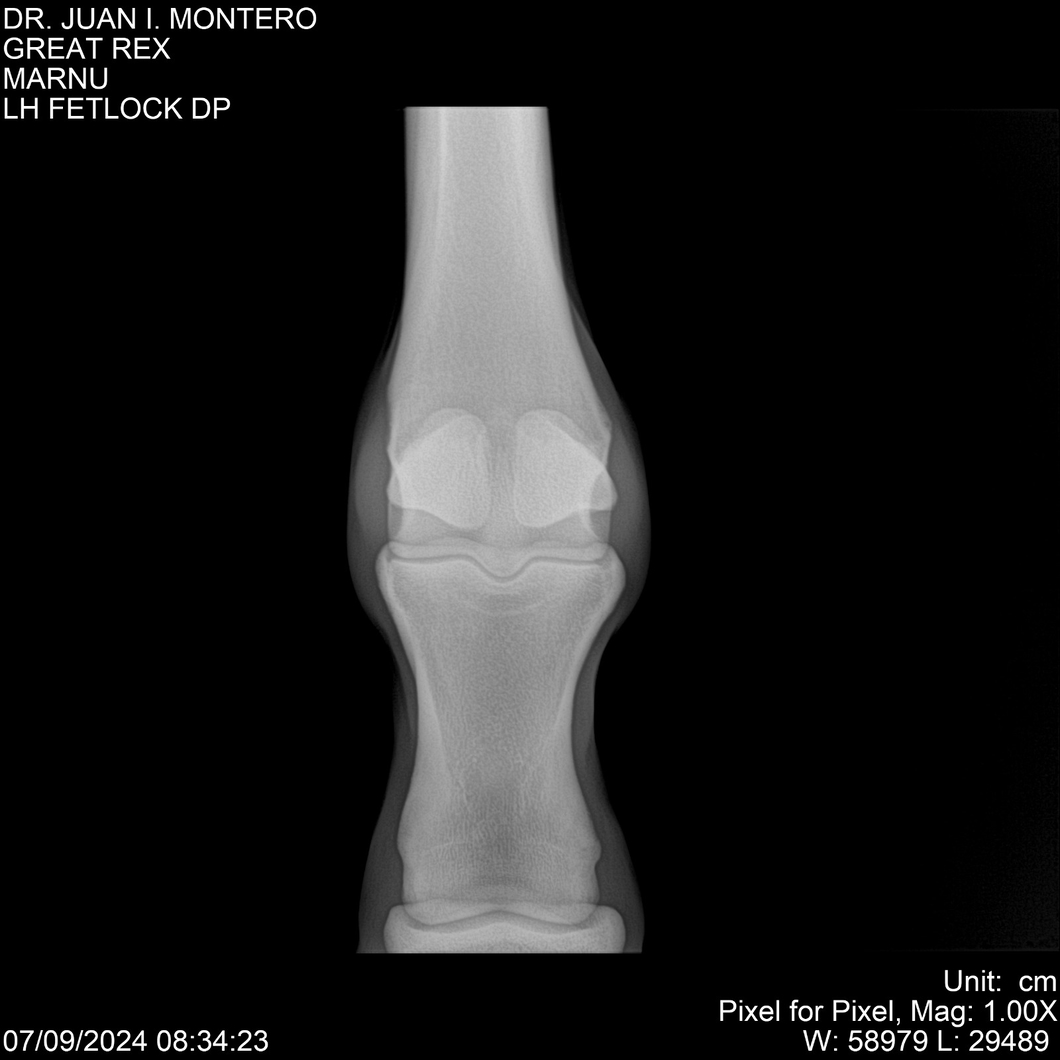

LOTE 4, GREAT REX Lote Anterior Volver al remate Lote Siguiente Ficha Contacto Montevideo - Ficha del Lote Identificador: #282518 Categoría: Yeguarizos Montevideo - 66 Visualizaciones ClicData Contacto Empresa: Abelenda N. R., Walter Hugo Nombre*: Teléfono* : E-mail* : Mensaje Enviar Registrese gratis Este contenido Exclusivo está disponible sólo para usuarios registrados Ingresar